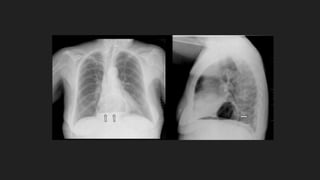

En base a esta imagen cual es su diagnostico:

En base enfrecuencia usted podría decir que el diagnostico de este paciente es: A esofago corto congenito B hernia hiatal por deslizamiento C Mixoma cardiaco D poliesplenia Que tratamiento seria mejor para este paciente: A transplante cardiaco B quimioterapia C radioterapia y quimioterapia de alto grado D Cirugia de Nissen En base a esta imagen cual es su diagnostico: A hernia de Bockdalek B hernia de Morgagni C Hernia hiatal Mixta D Hernia hiatal por deslizamiento

• #7 historia clínica detallada y examen físico RX DE TÓRAX. EL HALLAZGO DE UN NIVEL HIDROAÉREO SITUADO EN EL MEDIASTINO POSTERIOR EN LA RX. LATERAL DE TÓRAX SUGIERE LA EXISTENCIA DE UNA HERNIA DE HIATO. ESOFAGOGRAMA CON BARIO. CONFIRMA EL DIAGNÓSTICO. MÉTODO DIAGNÓSTICO DE ELECCIÓN. ESOFAGOGASTRODUODENOSCOPIA. INDICADO PARA DETERMINAR EL GRADO DE ESOFAGITIS, LA PRESENCIA DE ESTENOSIS, ESÓFAGO. DE BARRETT. LA HERNIA DE HIATO DESLIZANTE SE IDENTIFICA COMO UNA MUCOSA GÁSTRICA DE MAS 2 CM DE LONGITUD MANOMETRÍA. MOTILIDAD ESOFÁGICA. Esofagograma con bario aporta información importante sobre el tamaño del estómago herniado y la localización de la unión gastroesofágica, hernia hiatal las cuales son evidentes por este método si la herniación axial es de más de 2cm IMAGEN Esofagograma con medio hidrosoluble con evidencia de herniación de fondo gástrico por hiato esofágico

• #8 la radiografía de tórax se puede demostrar gas en las estructuras retrocardiacas Se puede observar una masa retrocardiaca con un nivel hidroaéreo. Cuando el aire se encuentra dentro de la hernia, la burbuja gástrica por debajo del diafragma tiende a estar ausente. Usualmente la hernia se encuentra a la izquierda de la columna vertebral, sin embargo las hernias de gran tamaño (particularmente las encarceladas) se pueden extender más allá de la silueta cardiaca y producir una mínima cardiomegalia. Estas hernias además del nivel hidroaéreo en su interior tienen contenido gástrico. (5) En las radiografías en posición supina el nivel hidroaéreo podría estar ausente; lo que dificulta la diferenciación con una masa retrocardiaca. El diagnóstico de las hernias pequeñas es más difícil y se debe realizar con el paciente en decúbito ya que se reducen en bipedestación